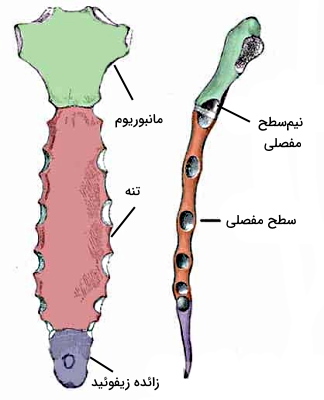

بخش استخوانی آناتومی قفسه سینه از «استخوان جناغ» (Sternum)، «دندهها» (Ribs) و «مهرههای سینهای» (Thorasic Spine) تشکیل شده است. استخوان جناغ یکی از استخوانهای پهن اسکلت بدن انسان است که در خط میانی قفسه سینه قرار دارد. این استخوان T شکل یکی از ساختارهای محافظتی اندامهای داخلی قفسه سینه است.

این استخوان از سه قسمت «مانبوریوم» (Manubrium)، تنه و زائده زیفوئید یا خنجری تشکیل شده است که در کودکی بهوسیله غضروف به هم متصل هستند. اما در بزرگسالی غضروفها به استخوان تبدیل شده و استخوان یکتکه جناغ بخشی از آناتومی قفسه سینه را تشکیل میدهد.

- استخوان مانبوریم: این قسمت بالاترین بخش استخوان جناغ و ذوزنقهای است. به فرورفتگی بخش بالایی این استخوان شکاف جگولار گفته میشود. بافت پیوندی و غضروف این بخش در تشکیل مفصل با انتهای میانی استخوان ترقوه، مفصلهای جناغ-ترقوه شرکت میکند. غضروفهای دو طرف این استخوان در تشکیل مفصل با دندههای یک و دو شرکت میکند. بخش پایینی این استخوان با تنه مفصل تشکیل میدهد.

- تنه: تنه بزرگترین بخش استخوان جناغ است که بخش بالایی آن در ایجاد مفصل با استخوان مانبوریوم و بخش پایینی آن با زائده زیفوئید مفصل تشکیل میدهد. این استخوان در دو طرف با دندههای ۳ تا ۶ مفصل تشکیل میدهد.

- زائده زیفوئید: زائده زیفوئدی کوچکترین بخش استخوان جناغ است. زائده زیفوئیدی از بافت غضروفی تشکیل شده است که در دهه چهارم زندگی به استخوان تبدیل میشود. بخش پایینی این استخوان همسطح دهمین مهره سینهای (T10) است و در بعضی افراد با دنده هفتم مفصل تشکیل میدهد.